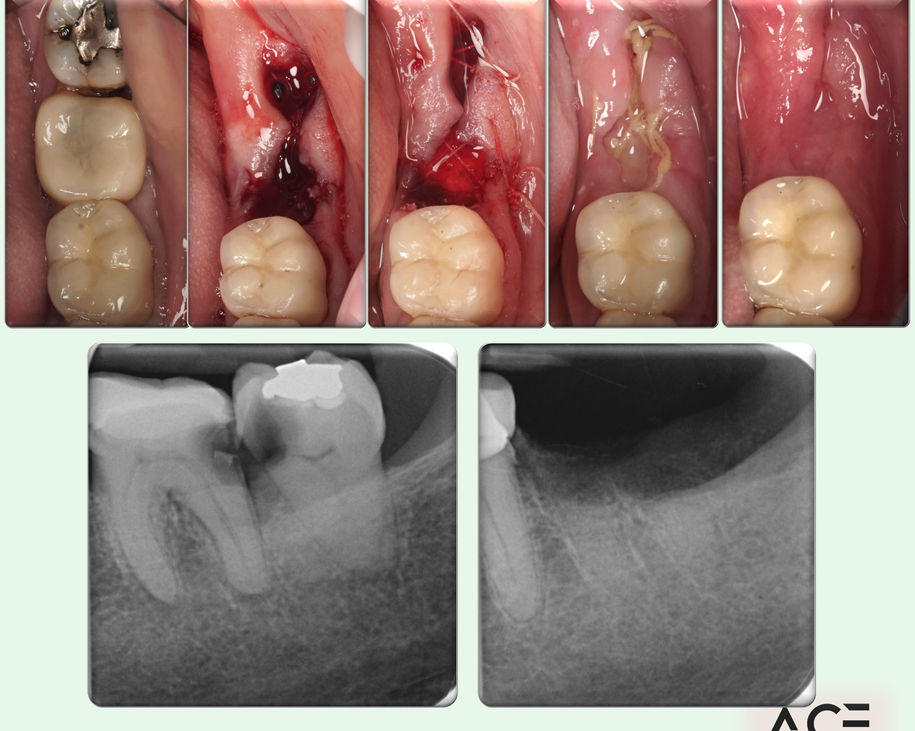

Alumni Outcomes showcasing below snippets of cases submitted as part diploma submissions

Dentists transitioning from routine dentistry into advanced restorative cases

Predictable clinical outcomes through structured protocols